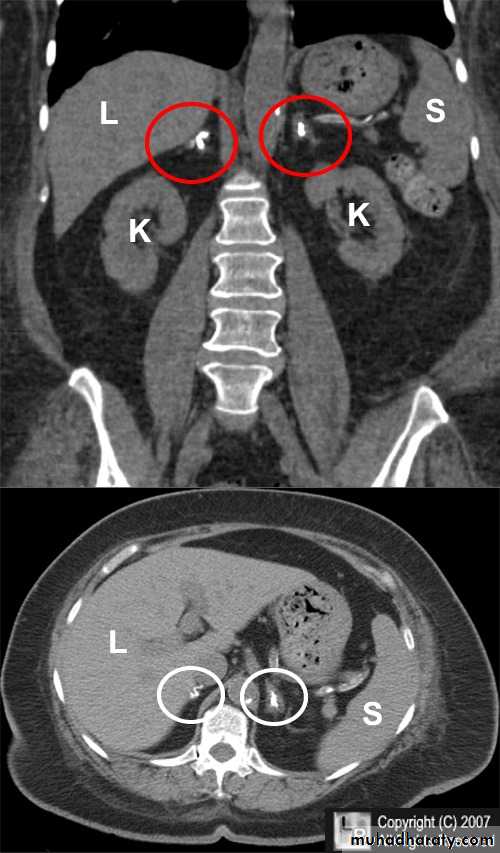

• Phaeochromocytoma is a tumour arising from chromaffin cells of the adrenal medulla.

• Ninety per cent occur in the adrenal gland and 10 per cent in ectopic extra-adrenal locations.

• Phaeochromocytomas are usually large tumors, measuring up to 12 cm with an average around 5 cm.

• Imaging of Phaeochromocytomas includes:

• CT of the abdomen, with particular attention to the adrenal glands is the initial imaging investigation of choice in the diagnosis of phaeochromocytoma.

• When the adrenal glands are normal on CT and no obvious mass is seen elsewhere, whole body scintigraphy with iodine labelled metaiodobenzylguanidine (131I-/123I-MIBG) may be useful.

• MRI of the abdomen may be used where MIBG is not available.